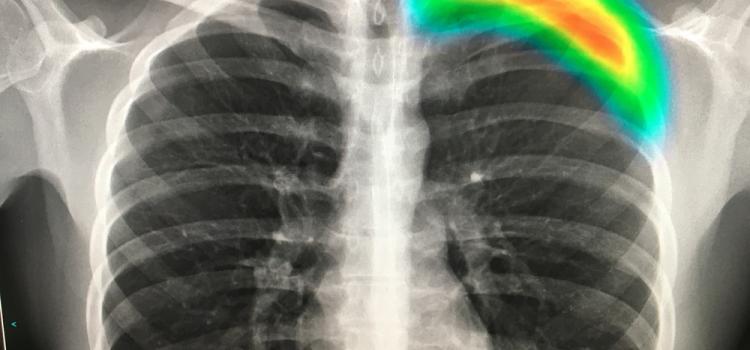

This technique provides better differentiation of items which may have similar composition. The colours represent different energy levels of the X-ray photons as recorded by the detector and hence identifying different components of body parts such as fat water calcium and disease markers. Please note that Art.

Detecting Covid 19 In X Ray Images With Keras Tensorflow And Deep Learning Pyimagesearch